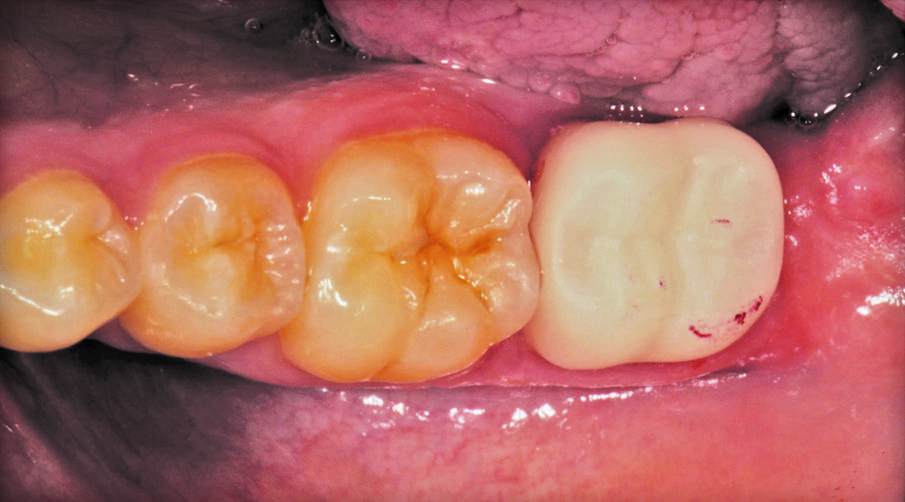

Fig. 16: Beautifully healed gingiva after three months.